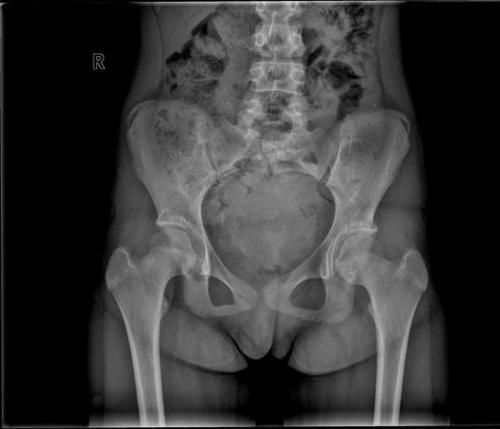

文章插图